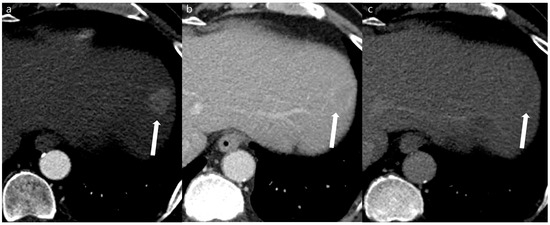

Figure 5. An 82-year-old man with a 0.5 cm sized enhancing nodule at segment 6 of the liver (arrows). A double low-dose CT using a deep-learning-based contrast-boosting model (a) shows better conspicuity (Reviewer 1, 5; Reviewer 2, 4) of the focal lesion (arrows) than standard-dose CT using hybrid iterative reconstruction (Reviewer 1, 5; Reviewer 2, 3) (b) at arterial phase images (time interval: 4 months). Two reviewers evaluated the double low-dose CT using deep-learning-based contrast-boosting model and standard-dose CT using hybrid iterative reconstruction. The results demonstrated no difference in overall image quality.